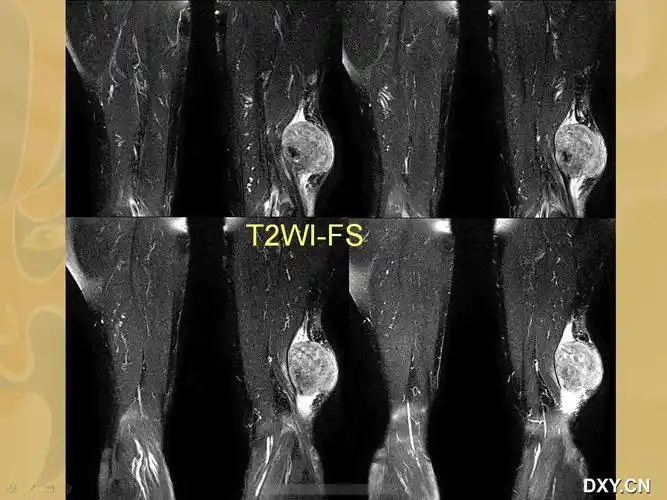

右大腿巨大肿瘤

女子左腿长50斤肿瘤

庄浪成功开展一例大腿巨大复发肿瘤切除术

老汉自以为的腿部肌肉原是大肿瘤 - 好大夫在线